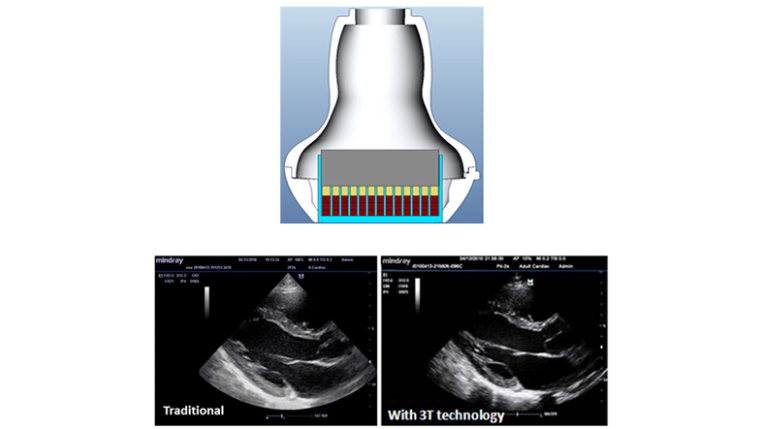

Tissue Doppler Imaging with Quantitative Analysis (TDI and TDI-QA)

Supported by MindrayŌĆÖs unique 3T technology with single crystal, the M7 premium significantly improves the performance of Tissue Doppler Imaging. With the added quantitative analysis package with comprehensive parameter outputs such as velocity, strain and strain rate, the TDI-QA performs with ease at the bedside.